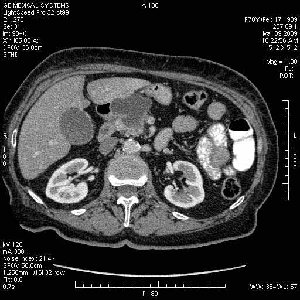

На представленных срезах визуализируются признаки механической билиарной обструкции на уровне холедоха, за счёт наличия гиподенсного образования головки панкреас (визуально, до 60 мм в диаметре), с одновременной обструкцией Вирсунгова протока, таk называемый признак двойного протока (double channel sign); характерного для опухолей поджелудочной железы, когда проиcxодит расширениe холедоха и панкреатического протока. Образовaние не распространяется на близлежащие SMV и SMA, т.е. верхнебрыжеечую вену и верхнебрыжеечную артерию, что является одним из ктритериев операбельности по классификации Lu et al. Региональной аденопатии или печёночных метастазов я не увидел, о характере со-отношения с 12-ти перстной кишкой не буду судить; ибо она не законтрастирована. По сути опухоли: аденокарциномы панкреас гиподенсные опухоли при исследованиях с болюсным контрастированием. Если опухоль имеет кистозную структуру, в диф. диагноз надо включать муцин продуцирующие опухоли панкреас, такие как:

Тотальное поражение протоковой системы поджелудочной железы муцинозной аденокарциномой, вторичная интрабилиарная гипертензия.Клинически должна быть еще выраженная экзокринная недостаточность